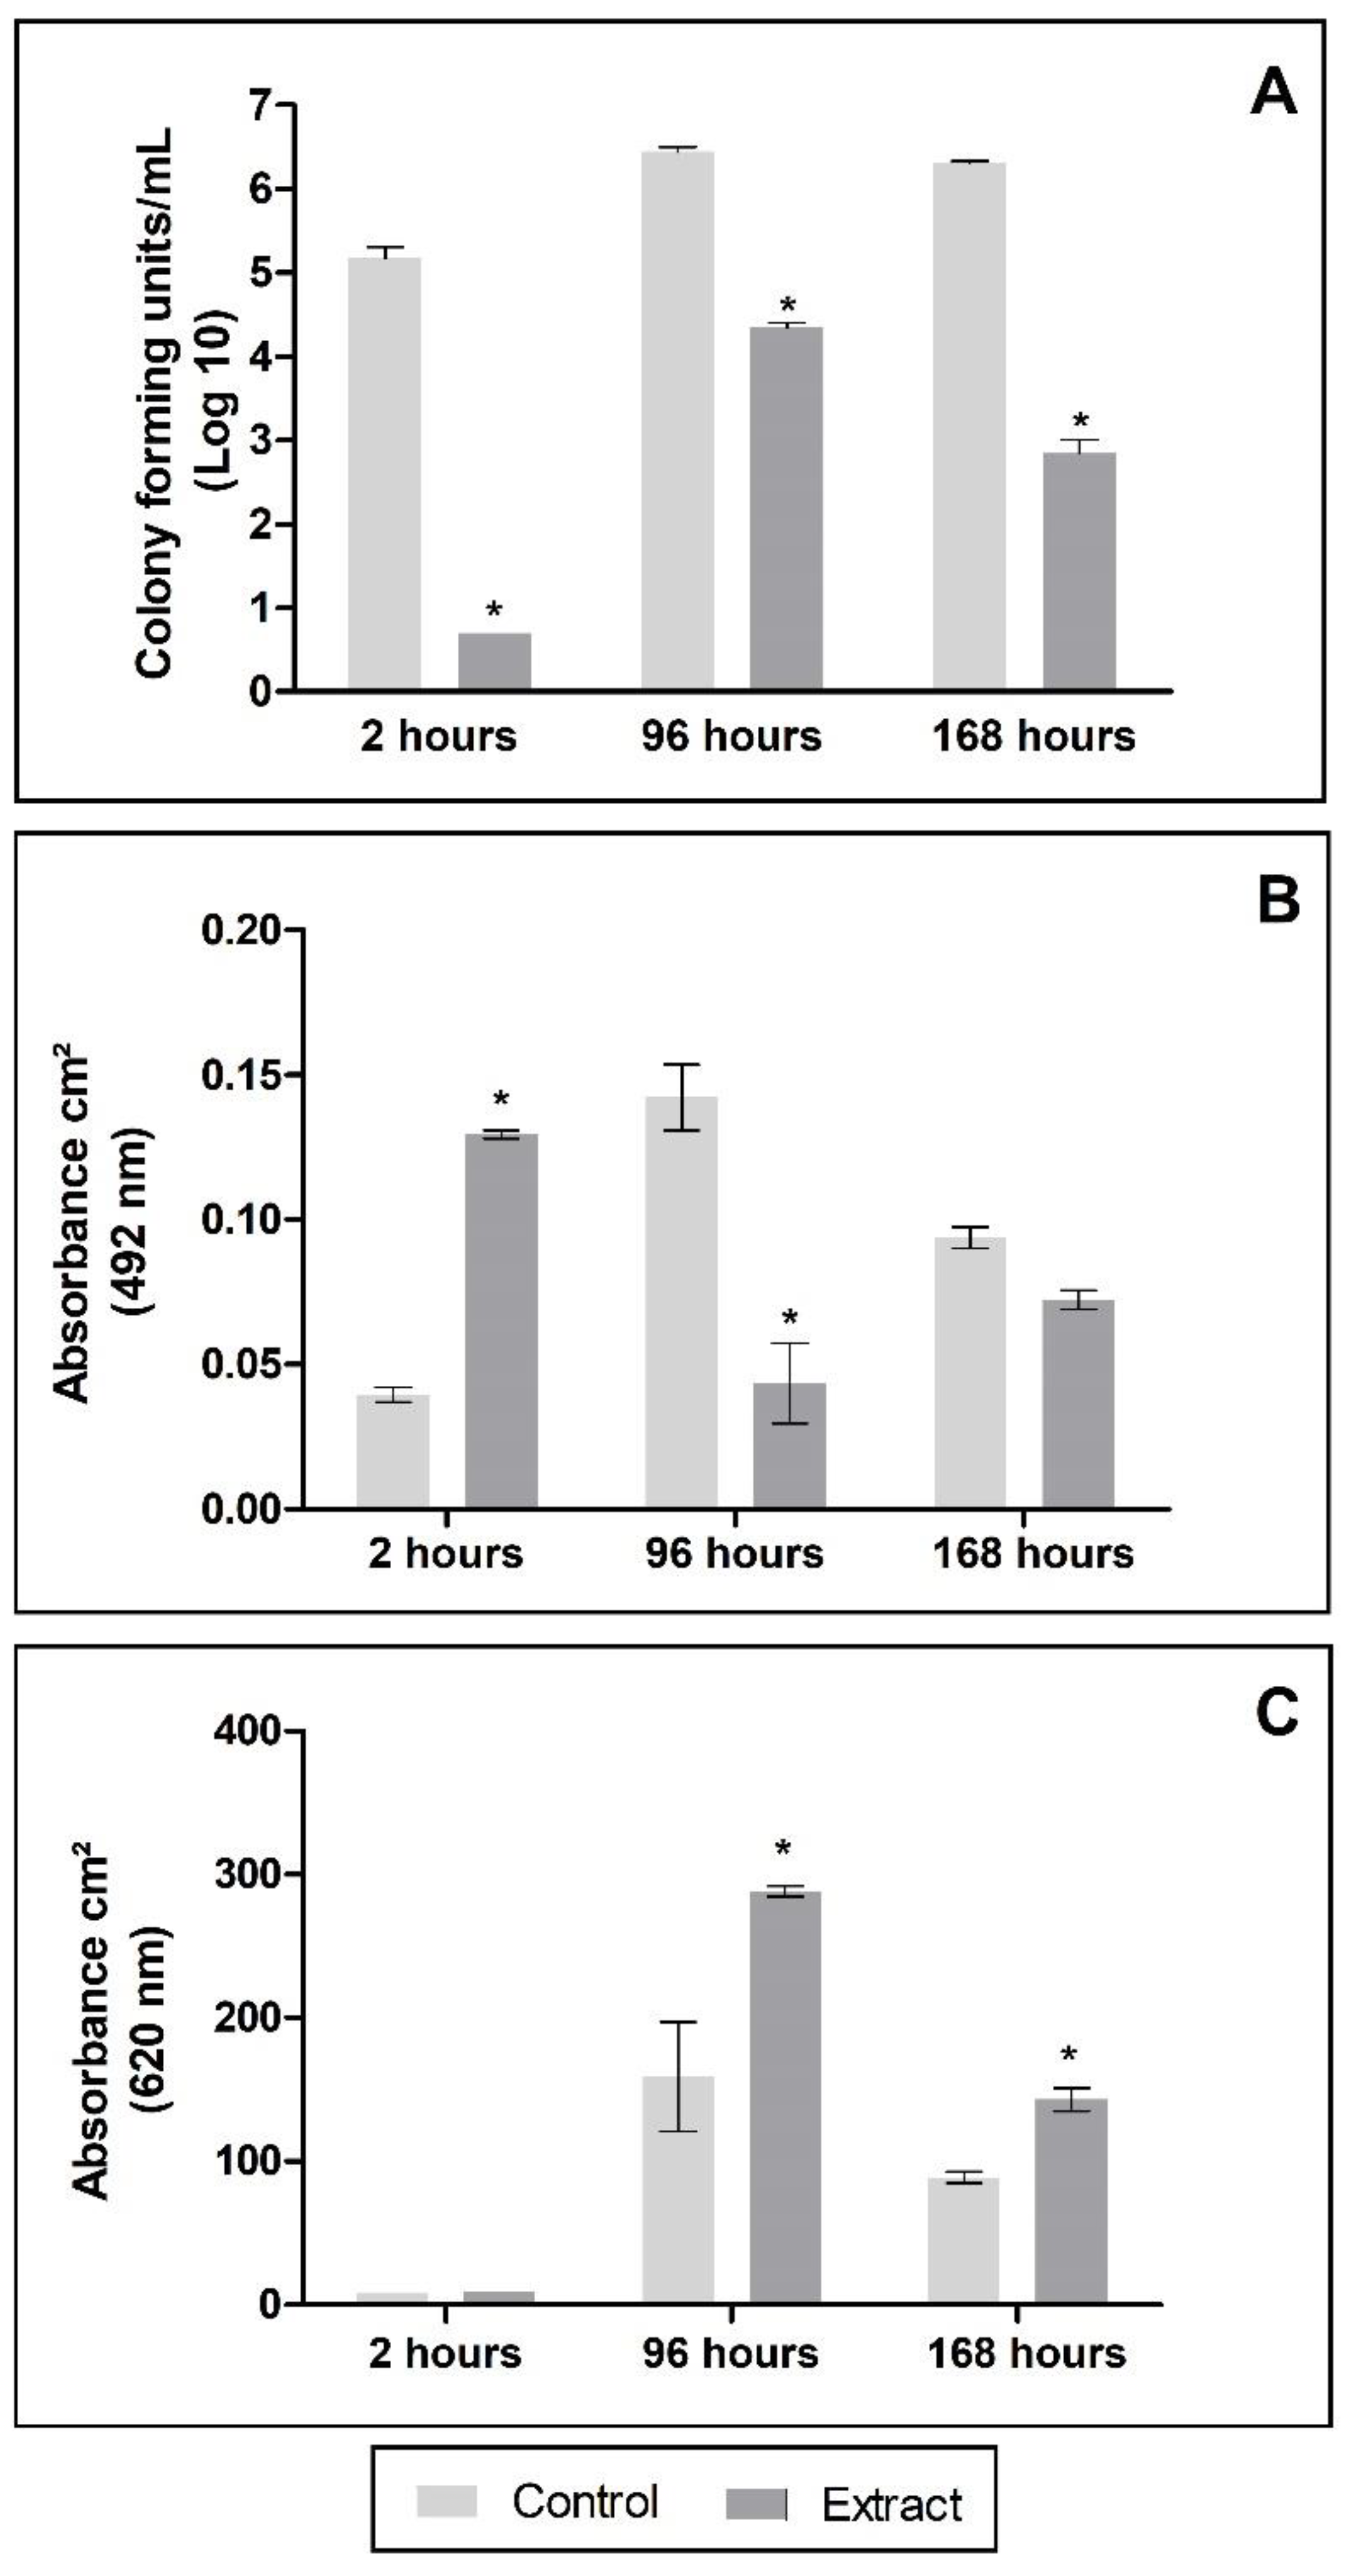

2.4.2. Antibiofilm Activity

2.4.3. Impact of PE Exposure to the Biofilm